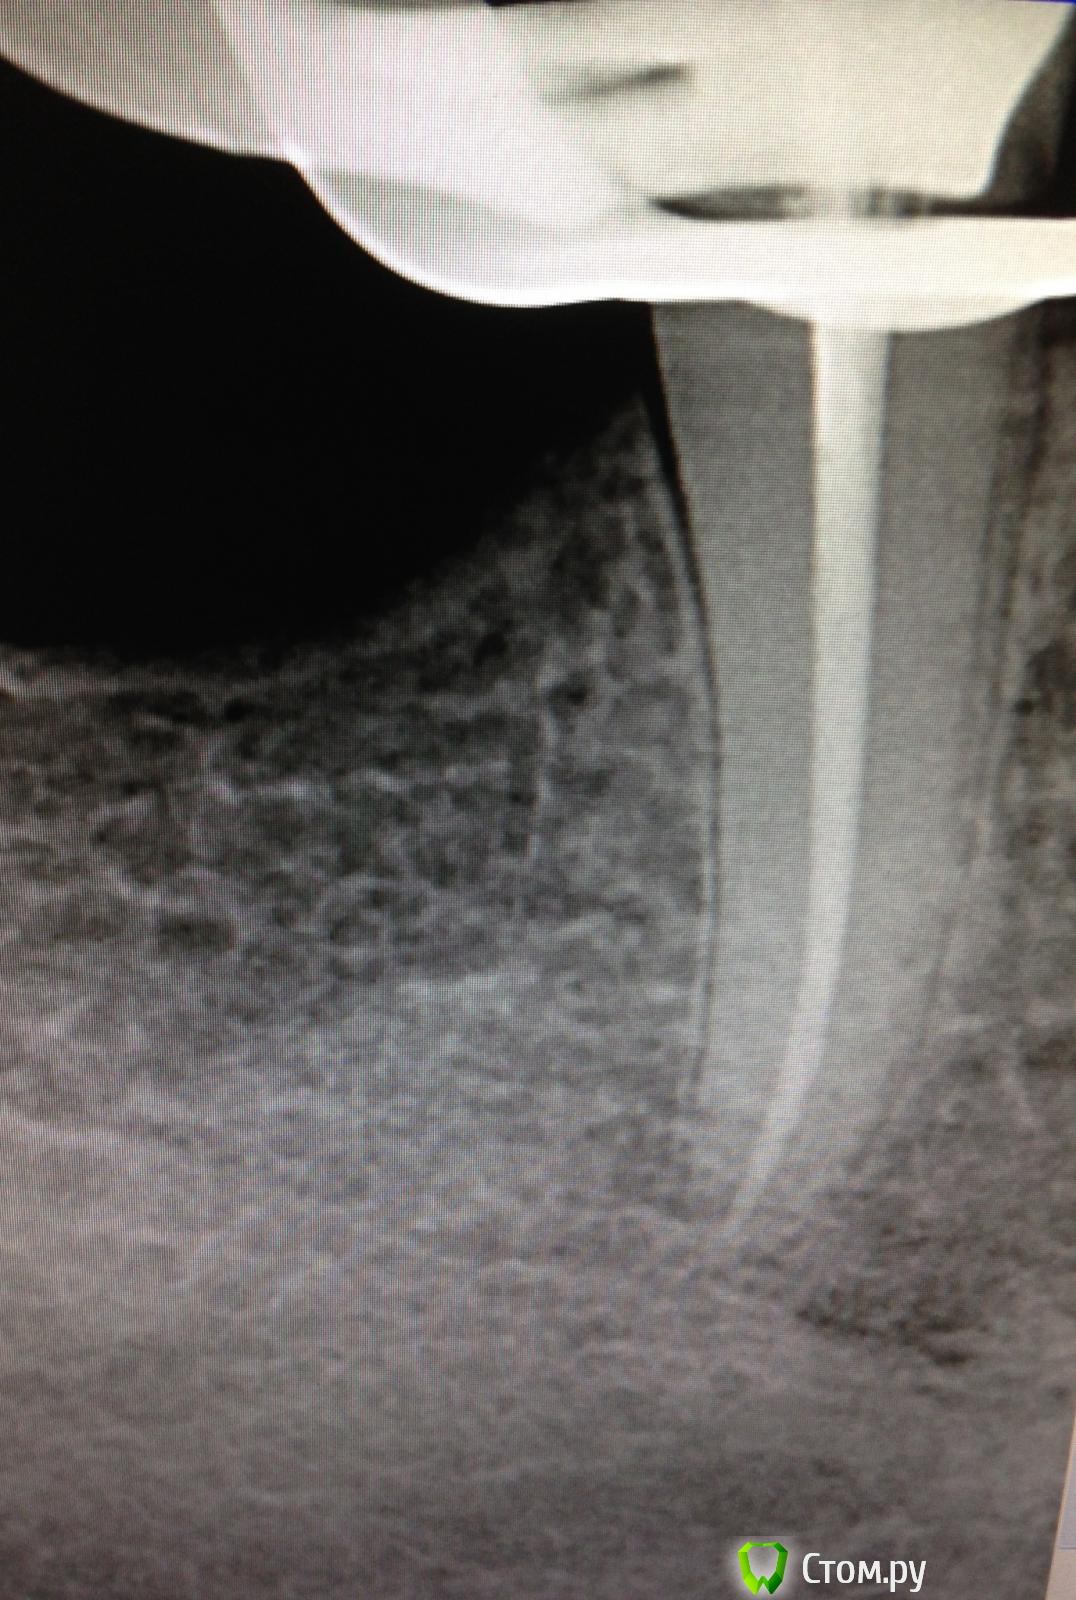

SSTi Опубликовано 26 мая, 2014 Автор Поделиться Опубликовано 26 мая, 2014 " Керамические "пульпиты( депульпировал по мк). 45. Дистально старая пломба. Доступ. Коффер. Протейперы машинные до ф2, профайлы, стоп упор 30.02. Гипохлор, аш два о, хлоргексидин. Уз. Латералка. 35. Стоп упор 40.02. Ссылка на комментарий